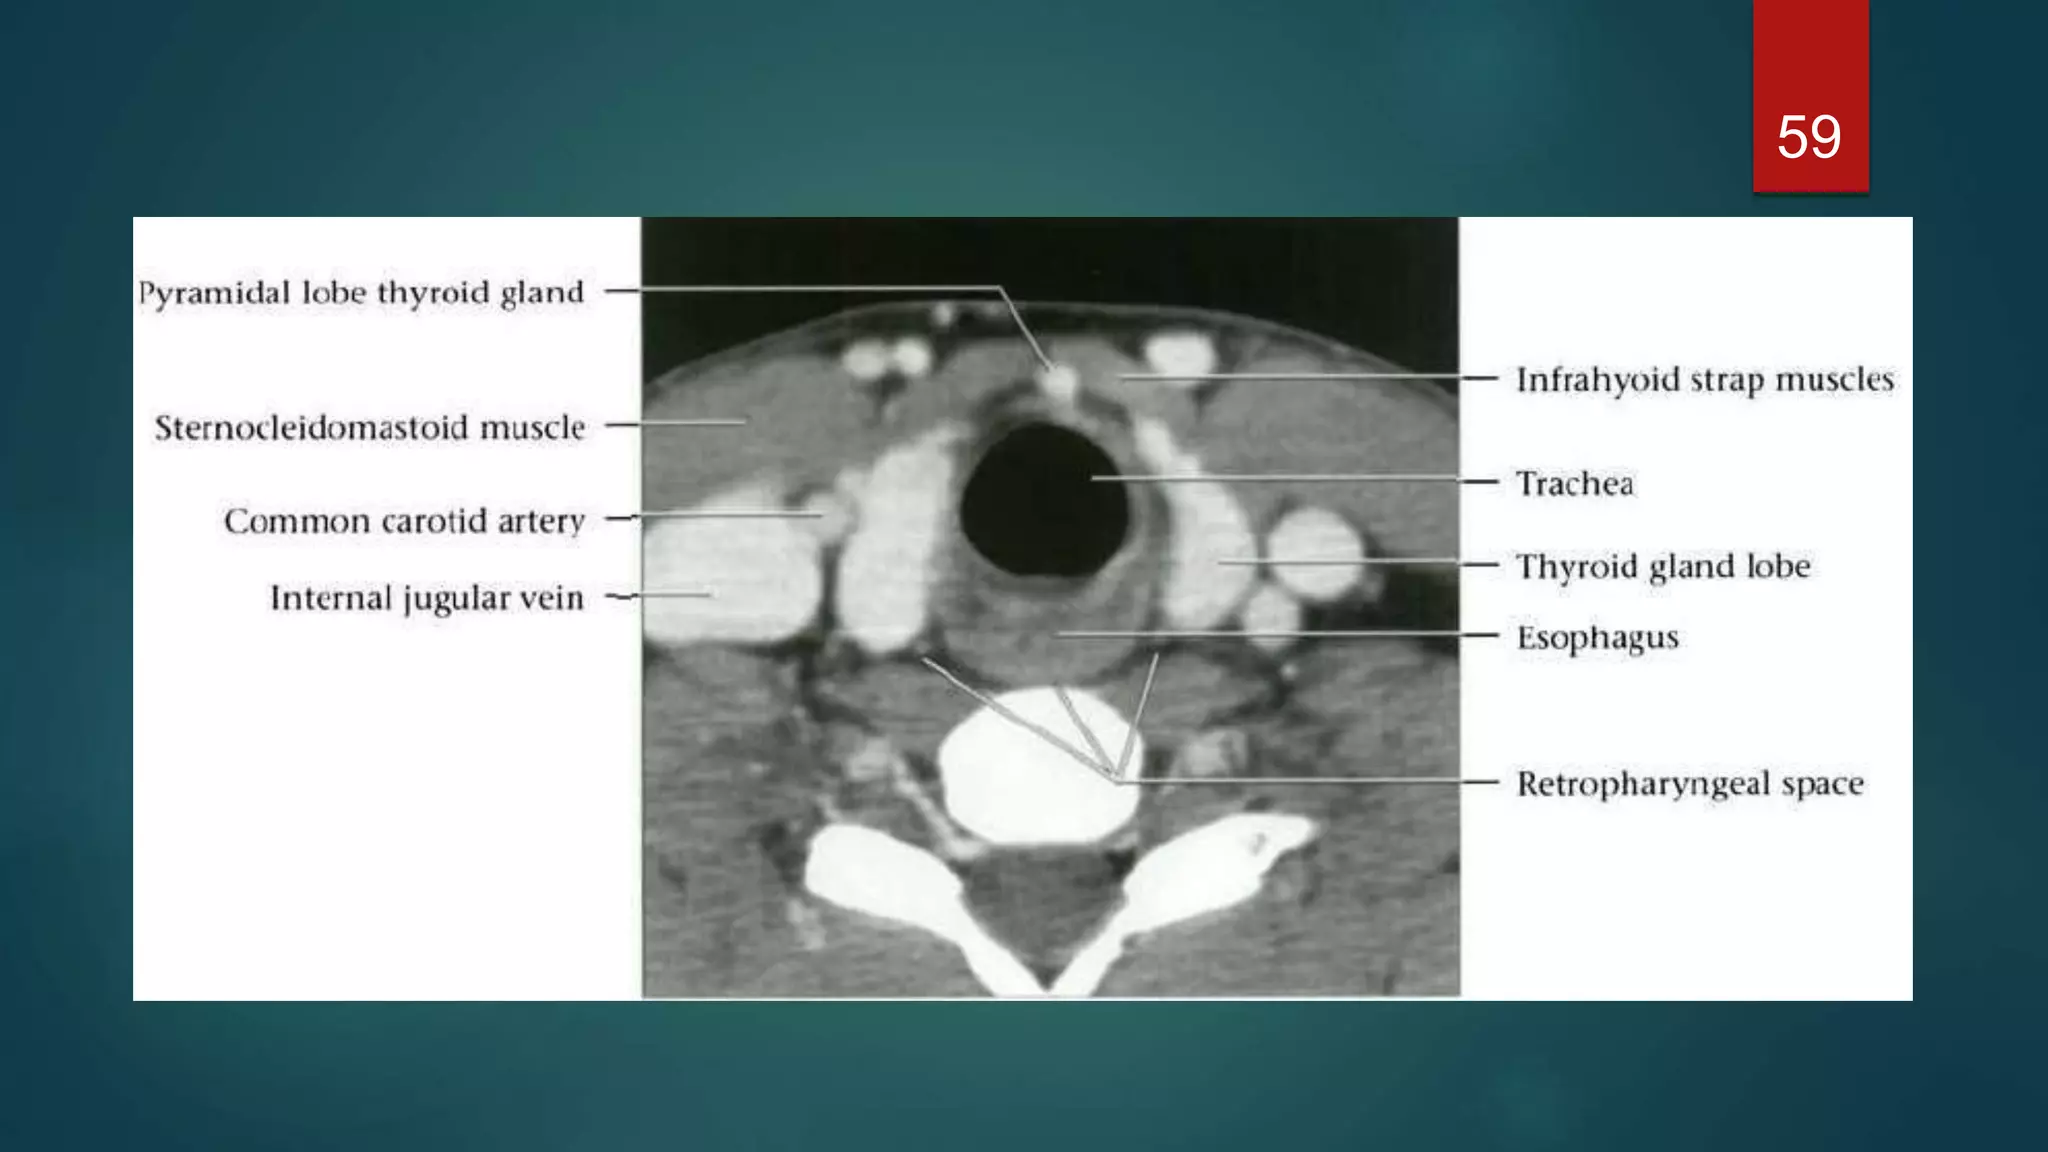

 The thyroid gland consists of two lateral lobes joined by a midline isthmus, and

lies anterior and lateral to the trachea.

 The lobes extend from the thyroid cartilage superiorly to the sixth tracheal ring

inferiorly

 Posterolaterally are the neck vessels, Behind these, on either side, are the

prevertebral muscles

 Anterior to the gland are the strap muscles of the neck and the sternomastoid

muscles

59